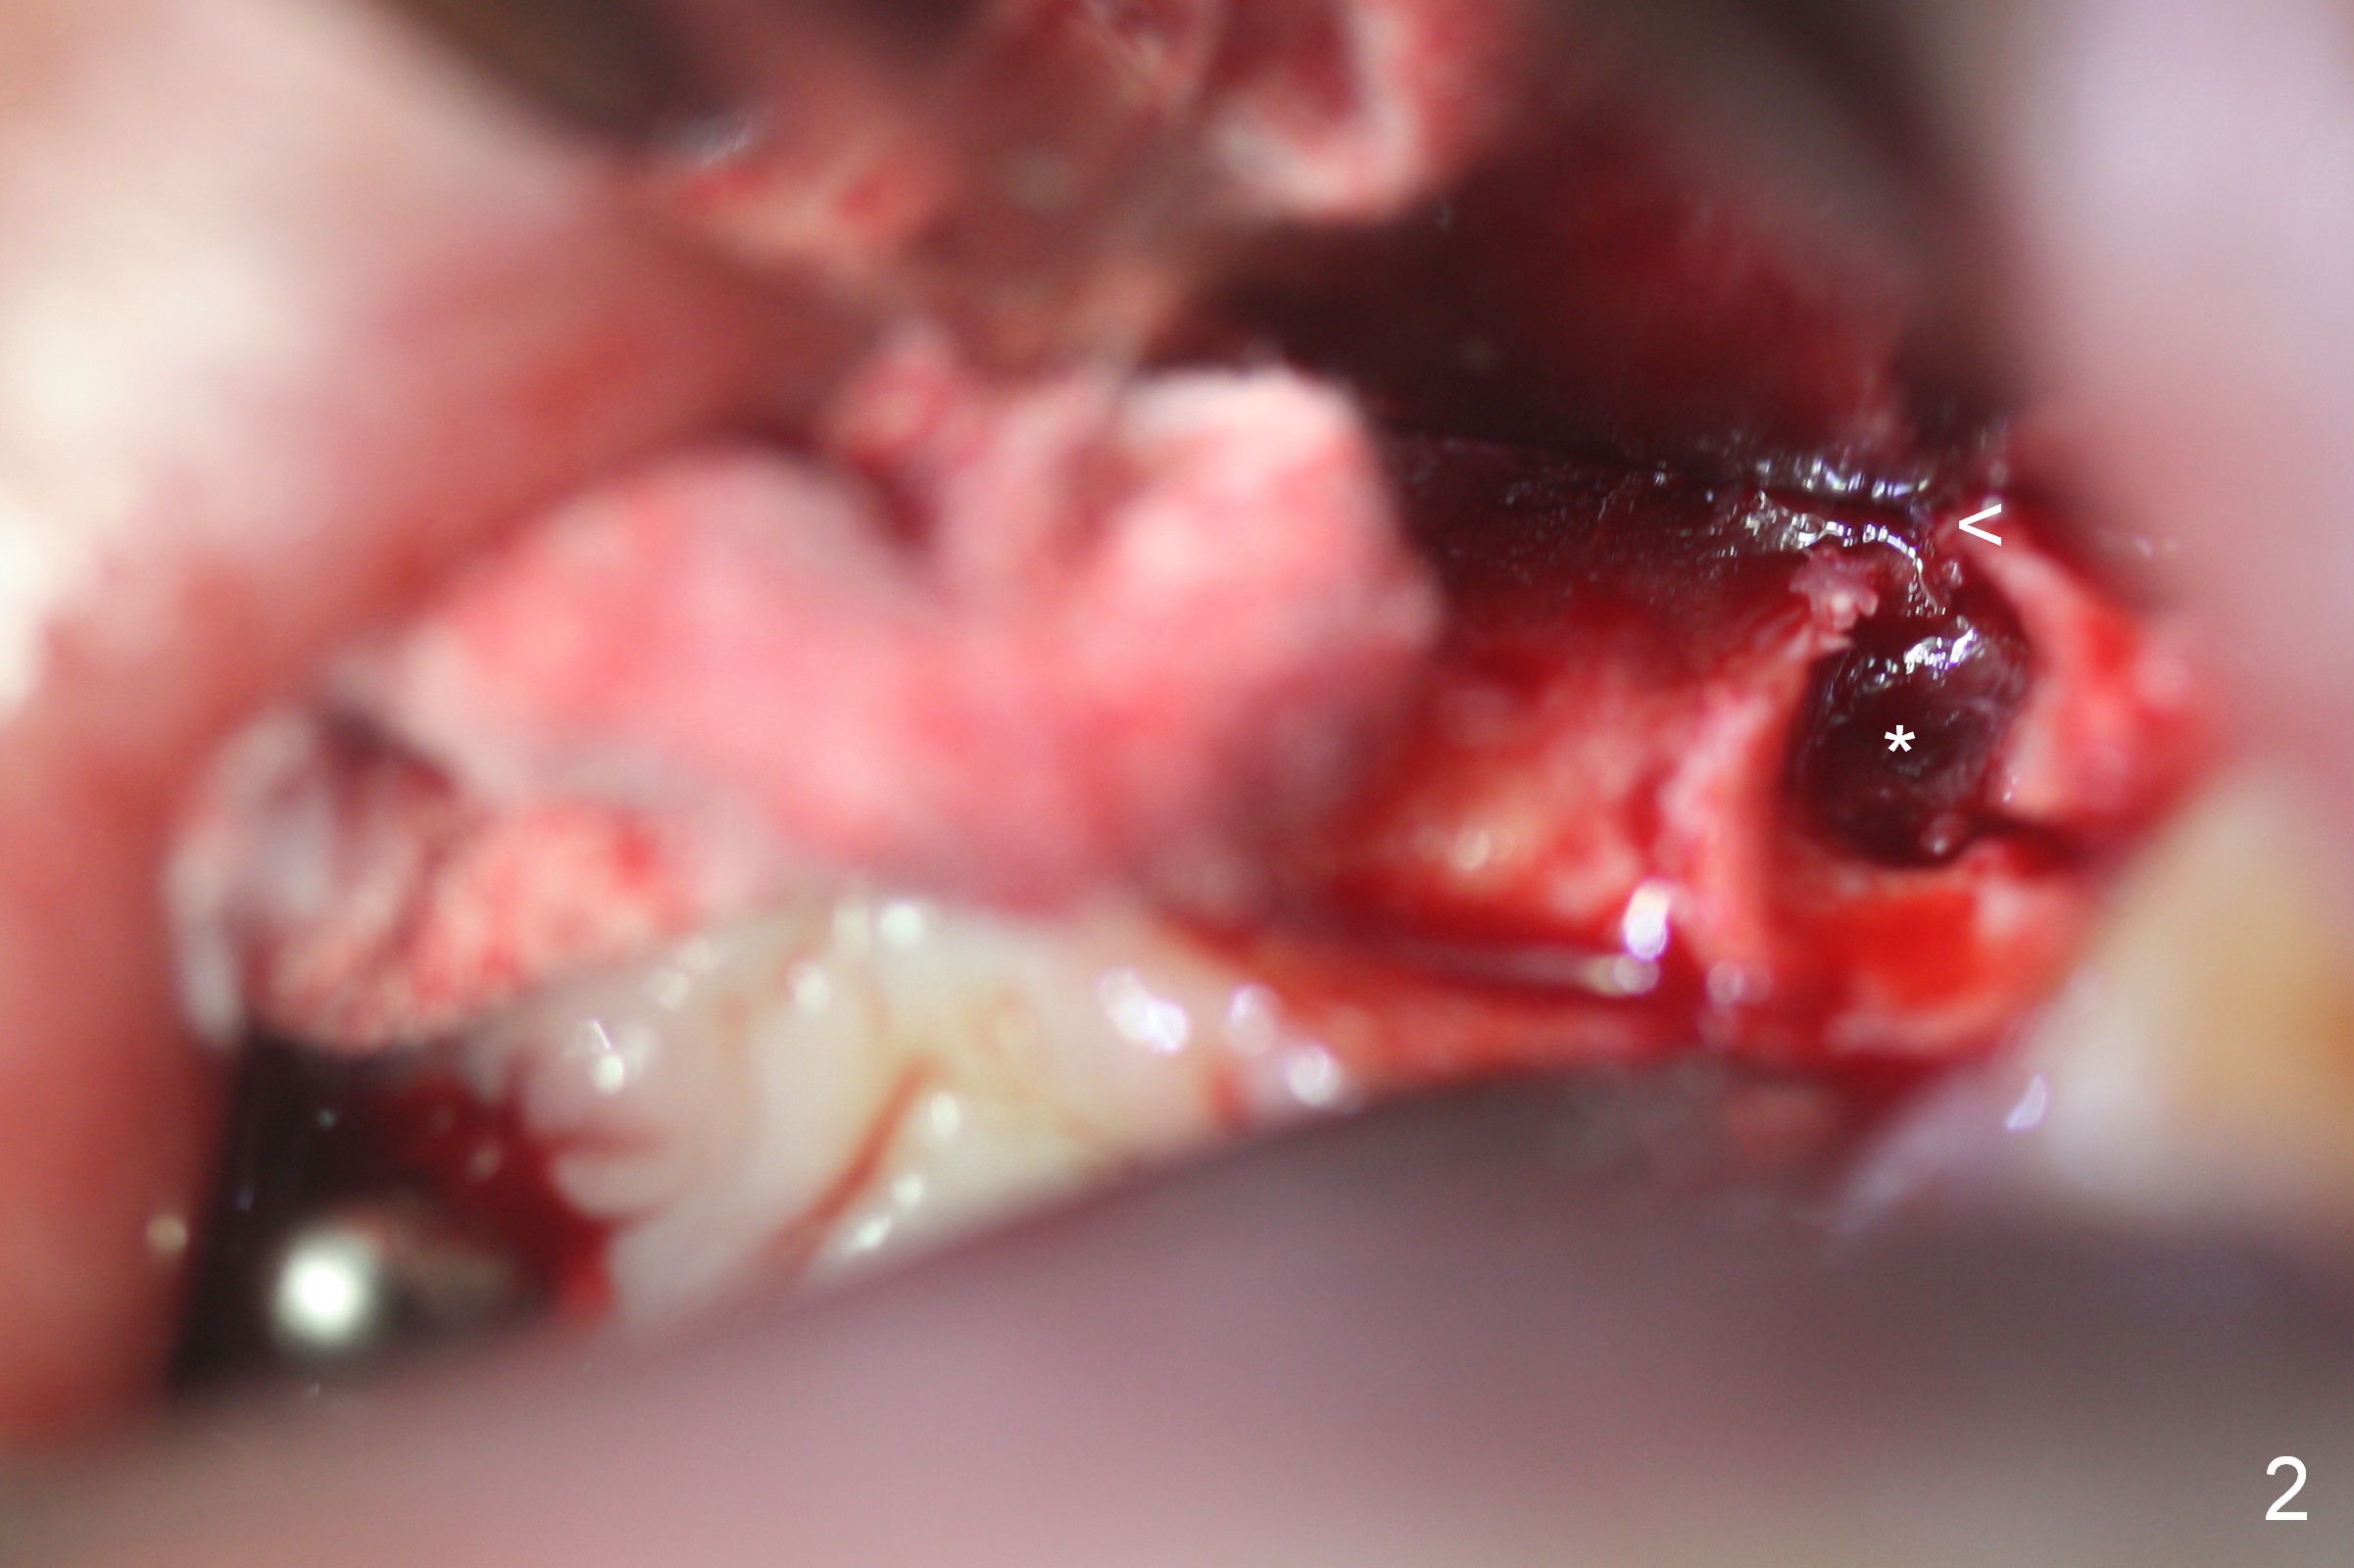

When the tooth #10 is extracted, the buccal plate has perforation (Fig.2 <) with granulation tissue in the socket (*). The socket is opened for better visibility and manipulation.